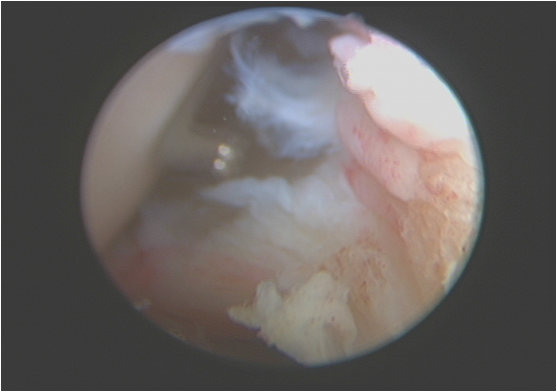

半月板缝合